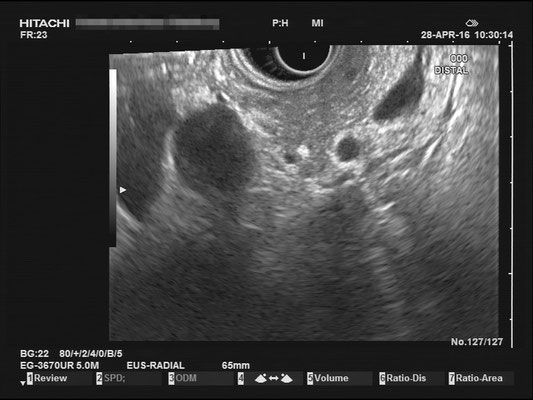

Common bile duct (CBD)

For a full examination of the common bile duct (CBD), we want have a great view of the most distal part, at the duodenal papilla. Optimally we can identify the double duct sign (or as I like to call it the "money shot") and work our way towards the liver. The CBD is joined by the hepatic artery and Portal vein, making up the Glisson's Triad. Using the doppler signal will help differentiate the vessels.

The most observant viewers will have noticed that not all images above depict normal findings but some abnormalities. (my bad ;)